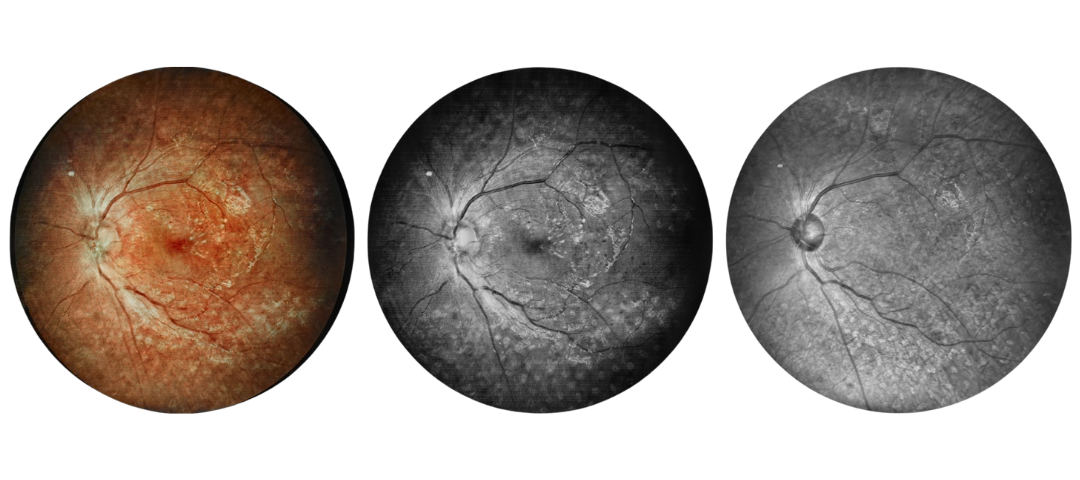

Fundus Cases Display

Our SLO makes fundus examination easier for you, capturing ultra-clear and wide-angle images of the retina and choroid, and then synthesizing color fundus images to present a rich picture of the fundus status.

Diabetic retinopathy: post photocoagulation

Diabetic retinopathy: bleeding and exudation

Diabetic retinopathy: bleeding, exudation and choroidal vascular abnormalities